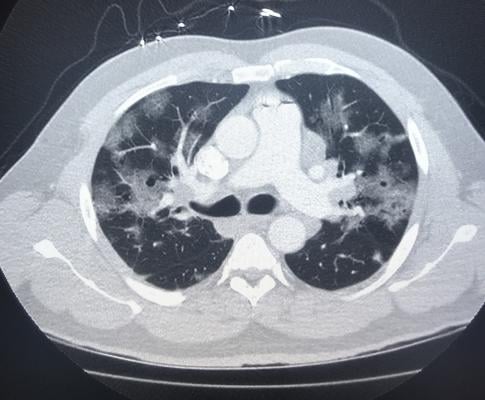

Covid19

Covid 19 Appearance On Ct